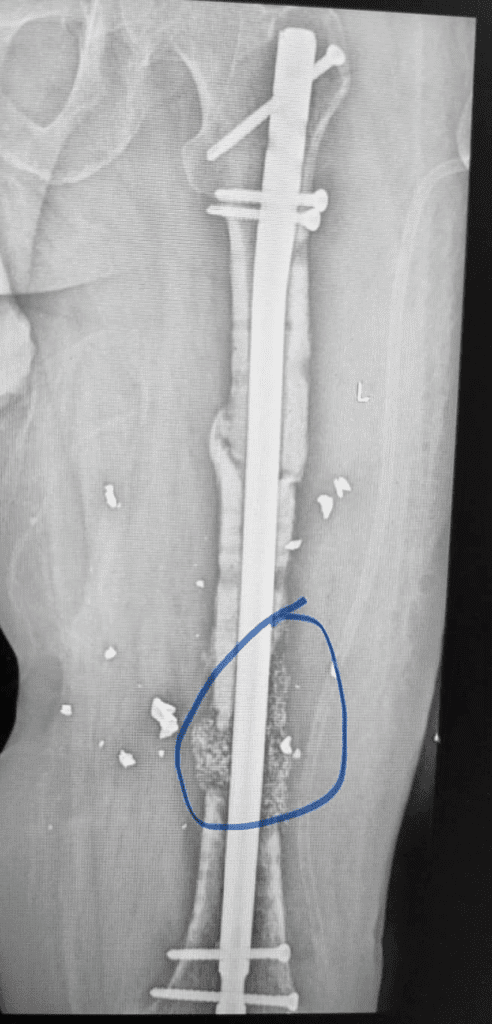

Тут вы видите рентгенограммы двух пациентов. В одном случае ранение голени у коленного сустава. В другом случае у сустава голеностопного с переломом костей. Поэтому там пластина еще стоит.

Обоим раненым (а каждый из них лечится по полгода уже) проведены по несколько операций дебридмента («чистка» кости и мягких тканей). К сожалению, это не остановило инфекцию.

В общем, все чаще и чаще приходится травматологам в Украине применять Bonalive. Это заменитель кости с антибактериальным действием. Только вот действует этот заменитель (финского производства) не за счет антибиотиков. Их в нем нет. А за счет того, что резко меняет Ph среды в кислую сторону. Бактерии погибают, привыкания к этому заменителю нет и быть не может (пока и если не появится какой-то новый, доселе неизвестный микроб), рост же собственной кости резко стимулируется.

Эти двое пациентов, чьи рентгенограммы вы видите, были прооперированы Председателем нашей Ассоциации AO Trauma Ukraine Олександром Рихтером в одном из военных госпиталей на западе Украины. Все зажило отлично.

Для первого раненого хватило 10 кубических сантиметров Bonalive, на второго – там, где пластина, ушло 20 «кубиков». Итого, в дополнение ко всему прочему – это 1500 евро.